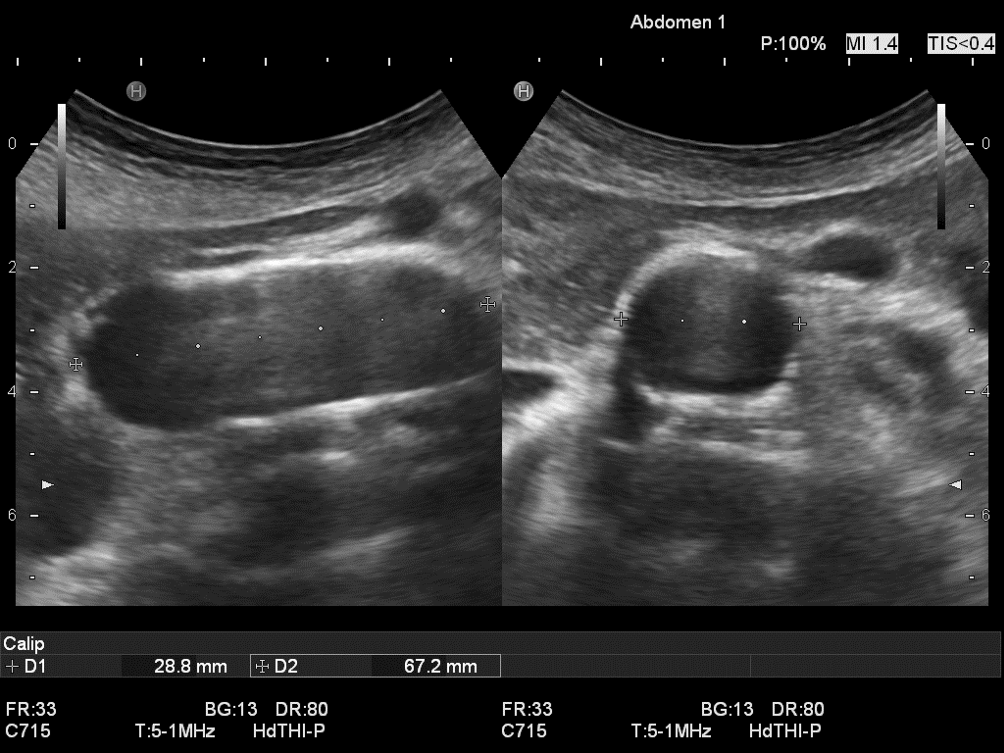

Abb. 1

Aortendurchmesser beim abdominalen Aortenaneurysma (AAA) mit Elongation nach links-lateral: Vergleich der axialen Messung im Oberbauchquerschnitt (links Durchmesser/D1 [in schräg transversaler Messachse] von 57 mm → Operationsindikation) mit der orthogonalen Messung, in welcher der Transducer an gleicher Stelle senkrecht zur Gefäßachse gedreht wurde (b/D2 von 47 mm und fast Rundstruktur → keine Operationsindikation). Diese orthogonale Durchmesserbestimmung (rechts) entspricht dem reellen Durchmesser (vgl. Videoclip 1). Der anterior-posteriore (a.-p.) Durchmesser ist gleichbleibend (44 mm bzw. 45 mm in D 3 und D 4)